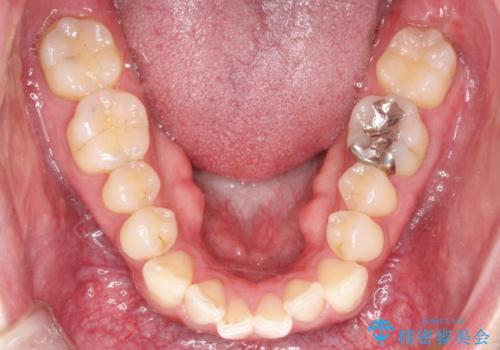

- 前歯の凸凹と顎の偏位を主訴に来院されました。

下顎の偏位を認めましたが、外科矯正を希望されなかったためできる範囲で顎の偏位を治すことができるよう治療を行なっております。

治療開始前に、下顎位の評価をおこなうことで、完成度の高い治療を行うことができました。